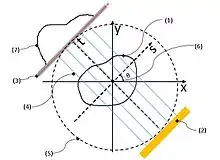

Schematic configuration and motion

In this section, the schematic configuration and motion of the parallel beam irradiation optical system configured to obtain the p(s,θ) of above-mentioned (eq. 5) will be explained. In this section, how to obtain the p(s,θ) of (eq.5) by utilizing parallel beam irradiation optical system will also be explained. Configuration and motions of parallel beam irradiation optical system, referring Fig. 3.

Numbers (1)–(7) shown in Fig. 3 (see the numbers within the parentheses) respectively indicate: (1) = an object; (2) = the parallel beam light source; (3) = the screen; (4) = transmission beam; (5) = the datum circle (a datum feature); (6) = the origin (a datum feature); and (7) = a fluoroscopic image (a one-dimensional image; p (s, θ)).

Two datum coordinate systems xy and ts are imagined in order to explain the positional relations and movements of features (0)–(7) in the figure. The xy and ts coordinate systems share the origin (6) and they are positioned on the same plane. That is, the xy plane and the ts plane are the same plane. Henceforth, this virtual plane will be called “the datum plane”. In addition, a virtual circle centered at the abovementioned origin (6) is set on the datum plane (it will be called “the datum circle” henceforth). This datum circle (5) will be represents the orbit of the parallel beam irradiation optical system. Naturally, the origin (6), the datum circle (5), and the datum coordinate systems are virtual features which are imagined for mathematical purposes.

The μ(x,y) is absorption coefficient of the object (3) at each (x,y), p(s,θ) (7) is the collection of fluoroscopic images.

The parallel beam irradiation optical system is the key component of a CT scanner. It consists of a parallel beam X-ray source (2) and the screen (3). They are positioned so that they face each other in parallel with the origin (6) in between, both being in contact with the datum circle (6).

These two features ((2) and (3)) can rotate counterclockwise [Notes 1] around the origin (6) together with the ts coordinate system while maintaining the relative positional relations between themselves and with the ts coordinate system (so, these two features ((2) and (3)) are always opposed each other). The ts plane is positioned so that the direction from a collimated X-ray source (2) to the screen (3) matches the positive direction of the t-axis while the s-axis parallels these two features. Henceforth, the angle between the x- and the s-axes will be indicated as θ. That is, parallel beam irradiation optical system where the angle between the object and the transmission beam equals θ. This datum circle (6) will be represents the orbit of the parallel beam irradiation optical system.

On the other hand, the object (1) will be scanned by CT scanner is fixed to xy coordination system. Hence, object (1) will not be moved while the parallel beam irradiation optical system are rotated around the object (1). The object (1) must be smaller than datum circle.

Obtaining transmission image ‘s’

During the above-mentioned motion (that is pivoting around the object(1)) of parallel beam irradiation optical system, the collimated X-ray source (2) emits transmission beam (4) which are effectively “parallel rays” in a geometrical optical sense. The traveling direction of each ray of the transmission beam (4) is parallel to the t-axis. The transmission beam (4), emitted by the X-ray source (2), penetrates the object and reaches the screen (3) after attenuation due to absorption by the object.

Consequently, a fluoroscopic image (7) is recorded on the screen as a one-dimensional image (one image is recorded for every θ corresponding to all s values). When the angle between the object and transmission beam is θ and if the intensity of transmission beam (4) having reached each "s" point on the screen is expressed as p(s, θ), it expresses a fluoroscopic image (7) corresponding to each θ.

Fig. 3 is intended to illustrate the mathematical model and to illustrate the principle of tomography. In Fig.3, absorption coefficient at a cross-sectional coordinate (x, y) of the subject is modeled as μ(x, y). Consideration based on the above assumptions may clarify the following items. Therefore, in this section, the explanation is advanced according to the order as follows:

By using a parallel beam irradiation optical system, one can experimentally obtain the series of fluoroscopic images (these are one-dimensional images of a specific cross section of a scanned object) for each angle between the object and the transmitted light beam. In Fig.3, the plane rotates counter clockwise. [Notes 1] around the point of origin in the plane in such a way “to keep mutual positional relationship between the light source (2) and screen (7) passing through the trajectory (5).” Rotation angle of this case is same as above-mentioned θ.